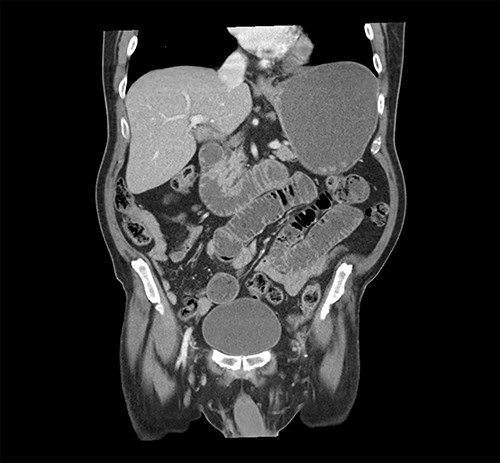

At the time of his PET scan, the patient acutely developed diffuse abdominal pain and vomiting. The scan was aborted and the patient was rushed to the emergency department. An abdominal X-ray and a CT scan of the abdomen and pelvis showed small bowel dilatation, but there was no intestinal mass lesion (Fig. 1). He was placed on nasogastric tube decompression. The patient reported having melena that morning. The hemoglobin was found to be 6.1 g/dl and a tagged RBC nuclear scan showed active gastrointestinal bleeding (Fig. 2) at the approximate location of the transition zone of the small bowel obstruction seen on CT.

CT of the abdomen and pelvis showing evidence of small bowel obstruction with dilated stomach and loops of the small intestine.